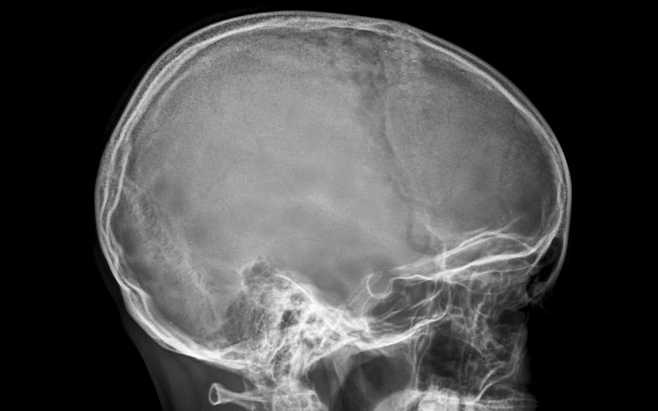

"몸에서 이런 변화 생기면 뇌 혈관 막힌 거예요" 바로 진료 권장합니다

특정 부위가 순간적으로 마비되거나 감각이 둔해지는 증상은 뇌혈관 문제의 대표적인 경고 신호입니다. 몇 분 내로 회복되더라도 ‘일과성 허혈 발작’일 가능성을 배제할 수 없습니다.

특히 한쪽으로만 나타난다면 즉시 병원 진료가 필요합니다. 반복되면 뇌졸중으로 이어질 위험이 커집니다.

갑작스럽고 강도가 높은 두통이 생기거나, 시야가 흐려지고 중심을 잡기 어려운 어지럼이 동반된다면 응급 상황일 수 있습니다.

“살면서 처음 겪는 두통”이라고 느낄 정도라면 즉시 응급실 방문이 권장됩니다. 지연될수록 후유증 위험이 커집니다.

뇌혈관 질환은 시간과의 싸움입니다. 증상이 사라졌다고 안심할 문제가 아닙니다.

한쪽 마비, 언어 이상, 갑작스러운 두통은 즉각적인 진료가 필요한 신호입니다. 몸이 보내는 경고를 무시하지 마세요. 빠른 대응이 뇌를 지킵니다.